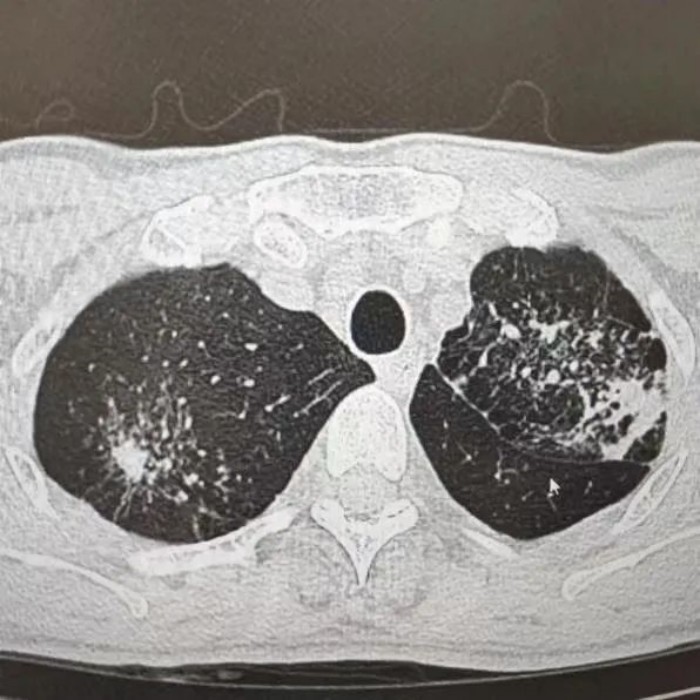

很快,CT報(bào)告提示“升結(jié)腸、回盲部及回腸末端腸壁增厚伴局部淋巴結(jié)腫大,考慮腸結(jié)核”。之后,進(jìn)一步做了胸部CT檢查,提示“肺部浸潤(rùn)灶:肺結(jié)核考慮”。

經(jīng)過(guò)痰化驗(yàn)及腸鏡檢查病理活檢,葉師傅被確診為“肺結(jié)核、腸結(jié)核伴腸梗阻”。